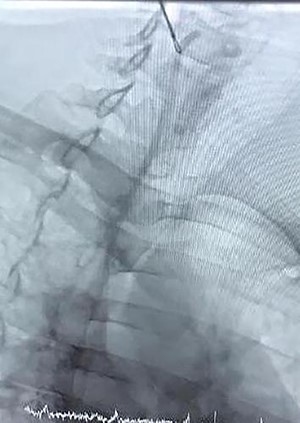

Case 3—a 5-year-old male child was diagnosed as having Hodgkin’s lymphoma during the evaluation of cervical lymphadenopathy and weight loss. He was planned for chemotherapy, and a central vein chemo port was implanted in a pediatric hospital. They took a chest X-ray (Fig. 4) after the procedure and understood the catheter is in the carotid artery instead of the jugular vein so they consulted with us and sent the child in <4 h to our vascular surgery operating room. We prepped and draped the neck of the child and removed the catheter from the carotid artery and packed it for 20 min. The child discharged the next day without any complication, and 10 days later in the clinic, he was fine.

Chemotherapy port catheter in the carotid artery of a 5-year old child.

Arterial puncture or cannulation with a sheath introducer or CV catheter is related to potentially devastating consequences. This happens at the carotid or subclavian artery in ~0.1% to a quarter of cases: 30% of those patients are often expected to become symptomatic, and if so, the death rate reaches 20–40% [1]. One must check whether the punctured site is compressible (by ultrasound) or not before he removes the inserted device. Puncture of the subclavian artery during subclavian vein catheterization attempts occurs in 0.5–4% of the patients. The subclavian artery cannot be compressed; so, the subclavian approach should be avoided in anticoagulated patients. The location of a CV catheter with the Seldinger technique could also be a choice for prevention. Percutaneous closure, balloon occlusion, covered stent placement, thrombin injection or surgical repair are used for treatment [1]. Within the case described here, the kid was referred to us in <4 h so we didn’t perform the other diagnostic imaging as we’d lose the time, then the catheter was removed, and therefore, the site of catheter insertion was packed. If the catheter remained for quite 6 h, we required proximal control of the artery, before resecting the catheter line and repair its puncture site with open surgery or by endovascular techniques (balloon occlusion, covered stent placement).